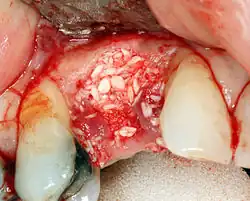

Additional procedures to augment deficient bone in implant site

For an implant to osseointegrate, it needs to be surrounded by a healthy quantity of bone. In order for it to survive long-term, it needs to have a thick healthy soft tissue (gingiva) envelope around it. It is common for either the bone or soft tissue to be so deficient that the surgeon needs to reconstruct it either before or during implant placement.[31]: 1084 All techniques of augmenting the alveolar bone in preparation for implant placement are invasive and associated with a degree of morbidity.[40]

Hard tissue (bone) reconstruction

Bone grafting is necessary when there is a lack of bone. It also helps to stabilize the implant by increasing survival rates of the implant and decreasing marginal bone level loss.[41] While there are always new implant types, such as short implants, and techniques to allow compromise, a general treatment goal is to have a minimum of 10 mm (0.39 in) in bone height, and 6 mm (0.24 in) in width. Alternatively, bone defects are graded from A to D (A=10+ mm of bone, B=7–9 mm, C=4–6 mm and D=0–3 mm) where an implant's likelihood of osseointegrating is related to the grade of bone.[42]: 250

To achieve an adequate width and height of bone, various bone grafting techniques have been developed. The most frequently used is called guided bone graft augmentation where a defect is filled with either natural (harvested or autograft) bone or allograft (donor bone or synthetic bone substitute), covered with a semi-permeable membrane and allowed to heal. During the healing phase, natural bone replaces the graft, forming a new bony base for the implant.[37]: 223

Three common procedures are:[42]: 236

- Sinus lift

- Lateral alveolar augmentation (increase in the width of a site)

- Vertical alveolar augmentation (increase in the height of a site)